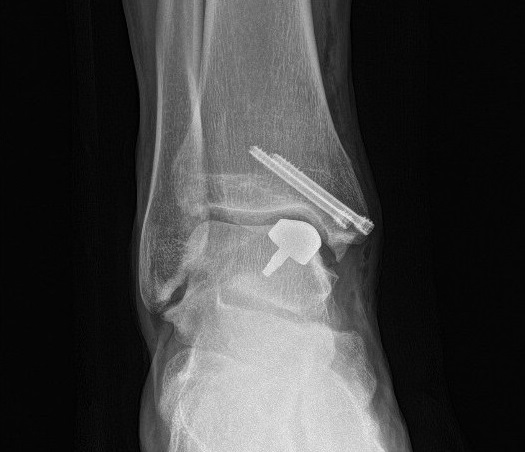

Using dedicated CT and MRI images of the ankle, a sort of "button" was made, a custom-made device with cobalt-chrome, titanium, hydroxyapatite alloy parts, which was implanted to replace the damaged cartilage and subchondral bone. The surgical instruments used for the operation were also designed and manufactured using 3D printing.